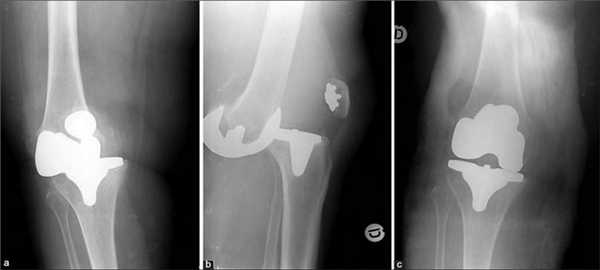

Одномыщелковая замена сустава на рентгене.

Как это выглядит после операции.

Имплант на рентгене.